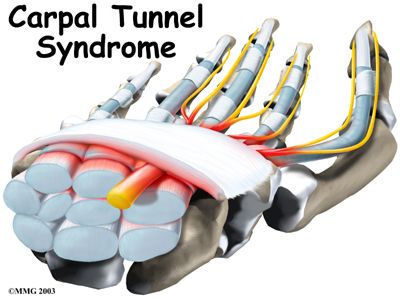

Carpal Tunnel Syndrome

Carpal tunnel syndrome (CTS) is a common problem affecting the hand and wrist. Symptoms begin when the median nerve gets squeezed inside the carpal tunnel of the wrist, a medical condition known as nerve entrapment. Any condition that decreases the size of the carpal tunnel or enlarges the tissues inside the tunnel can produce the symptoms of CTS.